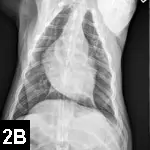

P**hysical ExaminationExamination findings included muffled heart sounds, poor peripheral pulses, pale mucous membranes with a CRT of 2 seconds, rectal temperature of 98.7°F, and distal extremities cool to the touch. ECG suggested ventricular premature contractions. Echocardiography revealed pericardial effusion and a right atrial mass (Figure 1**).

Figure 1. Echocardiography revealed pericardial effusion (asterisk) and a right atrial (RA) mass (arrow). (LA = left atrium, LV = left ventricle, RV = right ventricle)